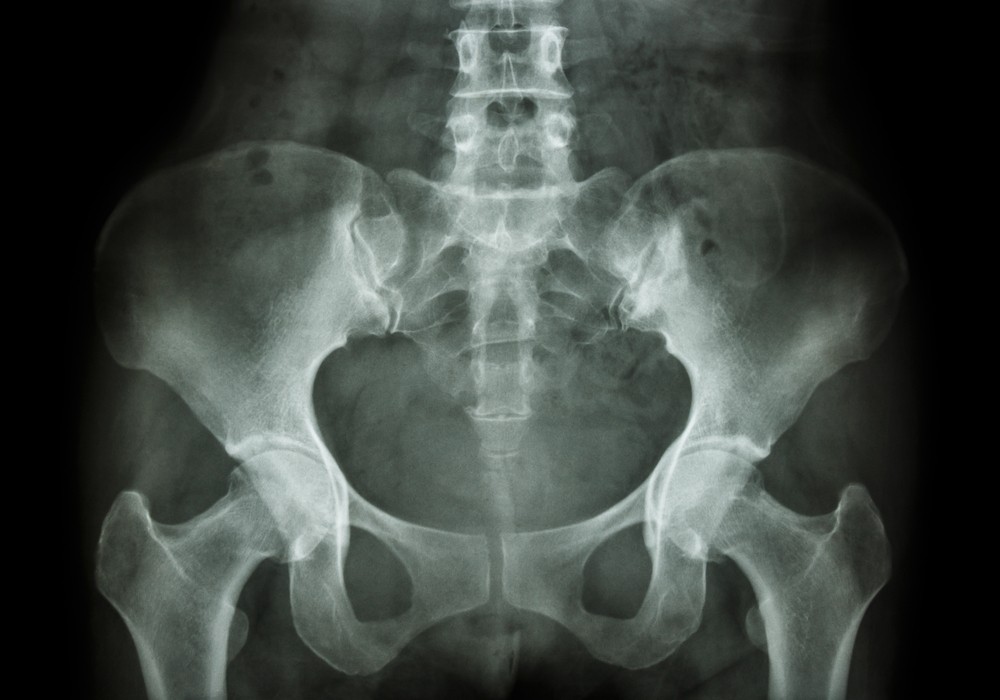

Что показывает рентген таза?

Рентгенография таза выявляет:

- онкологические процессы;

- доброкачественные опухоли;

- скопления метастаз;

- переломы костных структур;

- трещины;

- остеоартроз;

- подвывих тазобедренного сустава;

- остеопороз;

- некротические очаги;

- артрит;

- смещение, вывихи сустава;

- аномалии развития (приобретенные, врожденные);

- остеохондропатии;

- инородные предметы;

- воспалительные изменения.